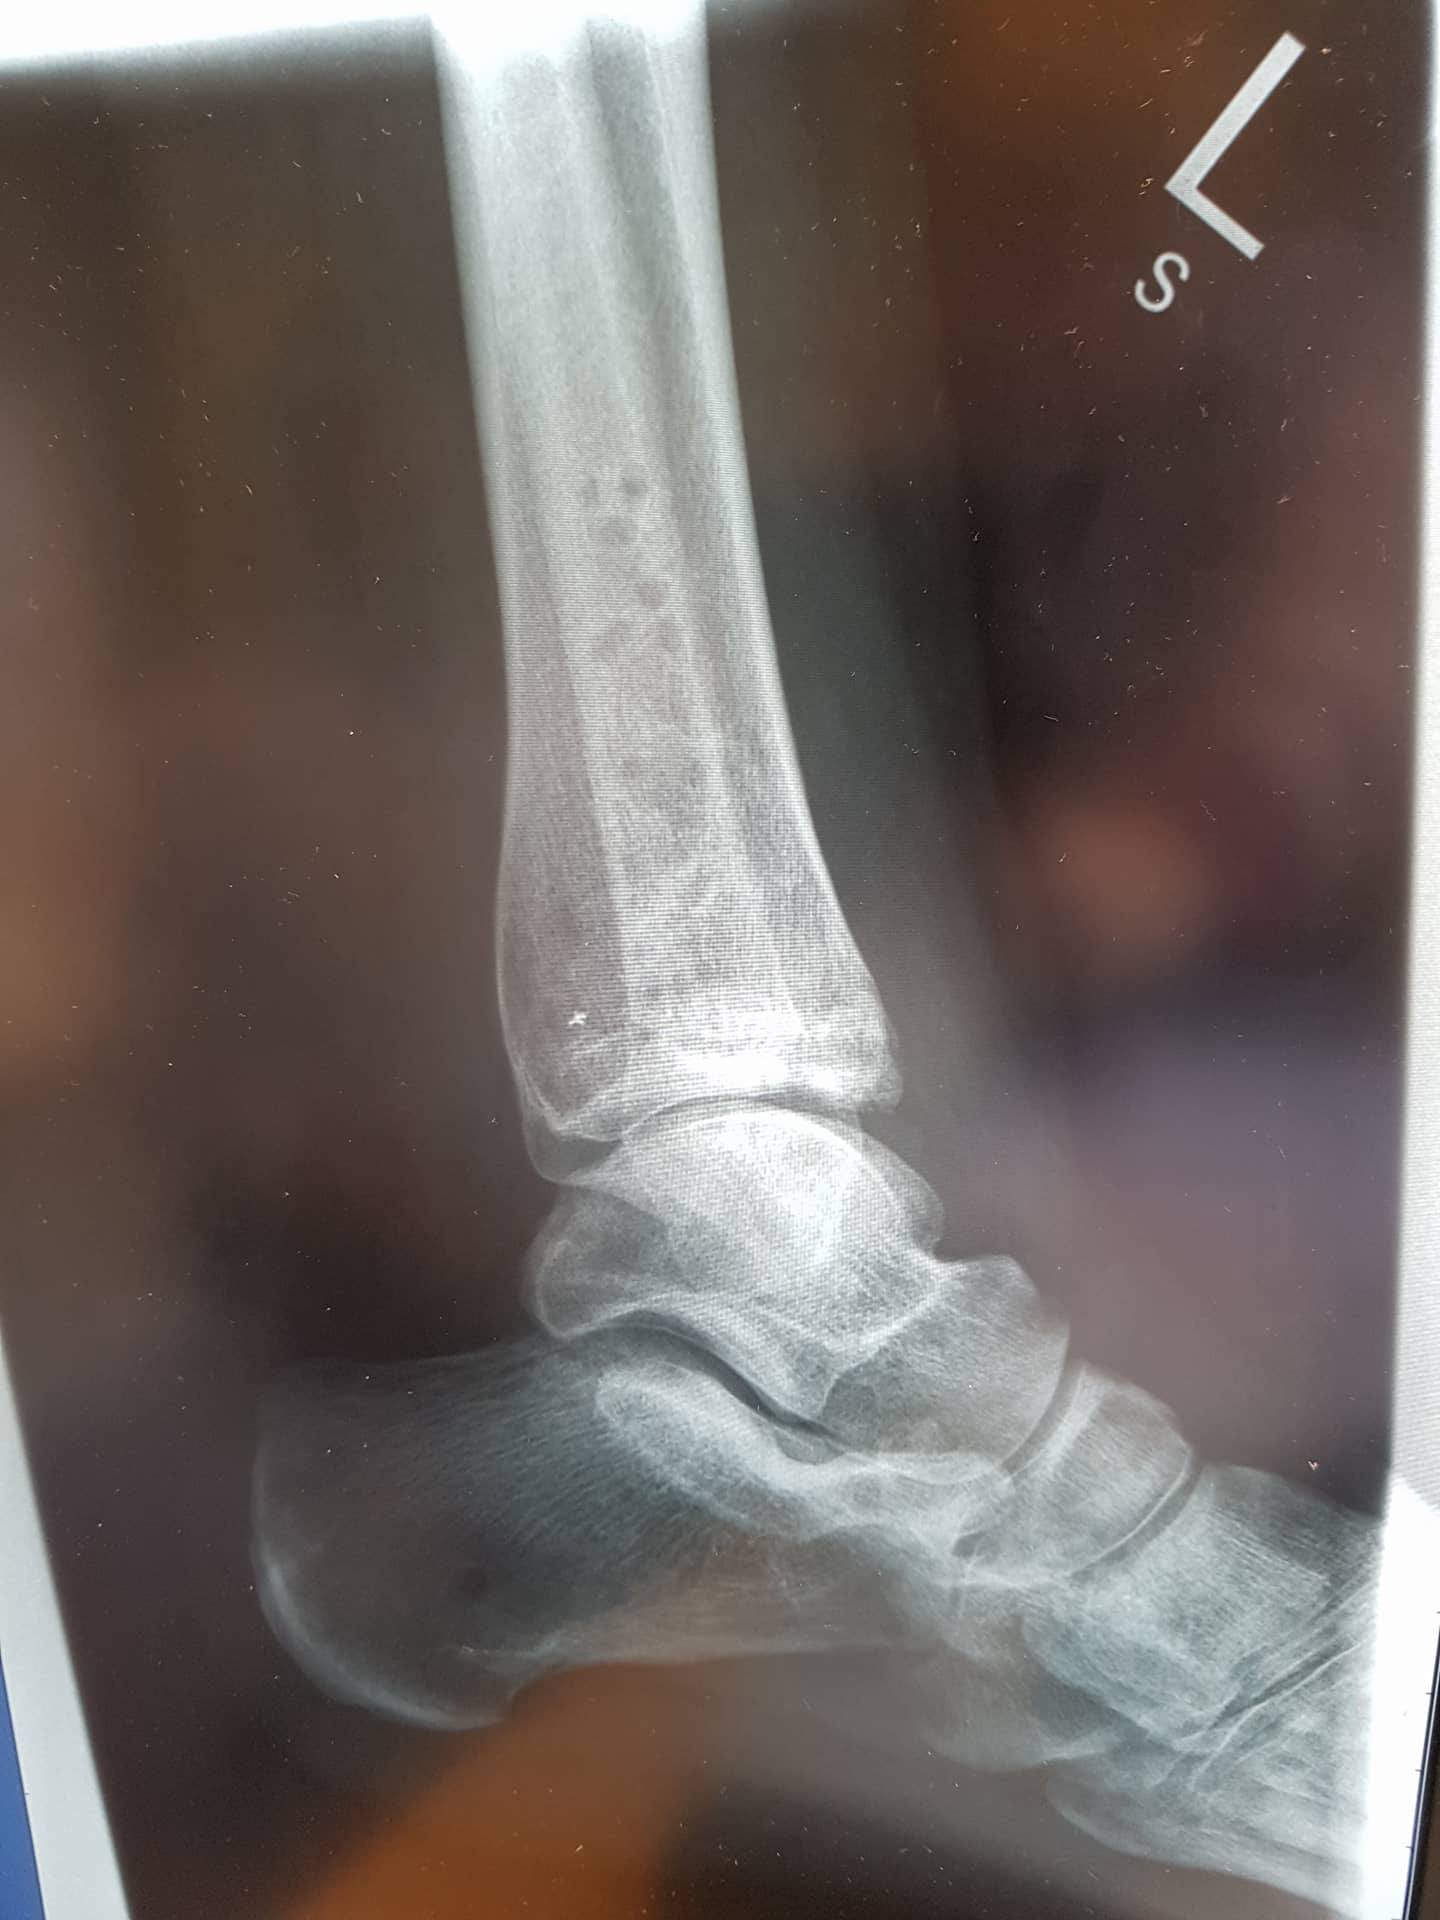

In this picture, you can see the ankle joint (the bit on the left), and the brand new joint I made myself by snapping the end off of the leg bone (the bit on the right). As you can see, the bit on the right has hardly healed. This was due to the infection, which was being harbored by the metal work. So, the metal work was removed. Next up, we have the x-rays that were taken this week:

The second above picture is taken from the same angle as the previous x-ray. As you can see, the bone is healing! This means that I most likely won’t need more surgery, hooray!

My leg bones however now look quite odd; you can see the holes from where the pins were. I had assumed that the surgeon would have filled them in with something, but I guess it does make sense to let them naturally fill in with bone. In the side on x-ray you can also see a fleck of white towards the back of the leg bone. This is a bit of shrapnel that came off from the pins during removal. This will likely live there for life, and hopefully won’t cause me any issues!